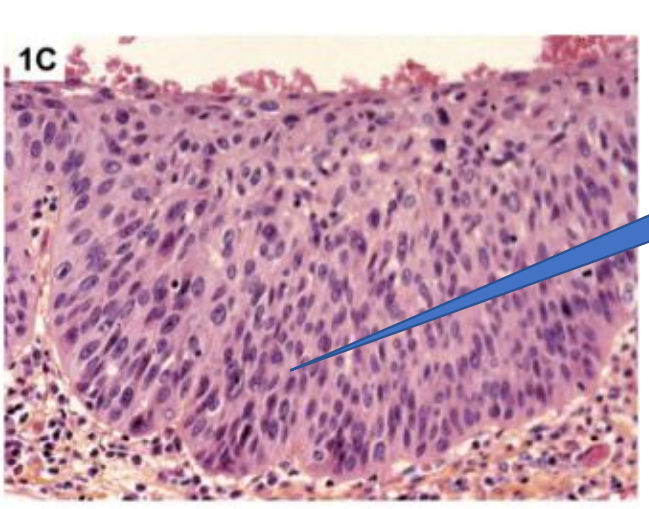

Dysplasia

—> normal stratified squamous epithelium

—> Dysplasia

Dysplastic signs

irregular stratification

nuclear and cellular pleomorphism

hyperchromasia

loss of polarity

abnormal mitotic features